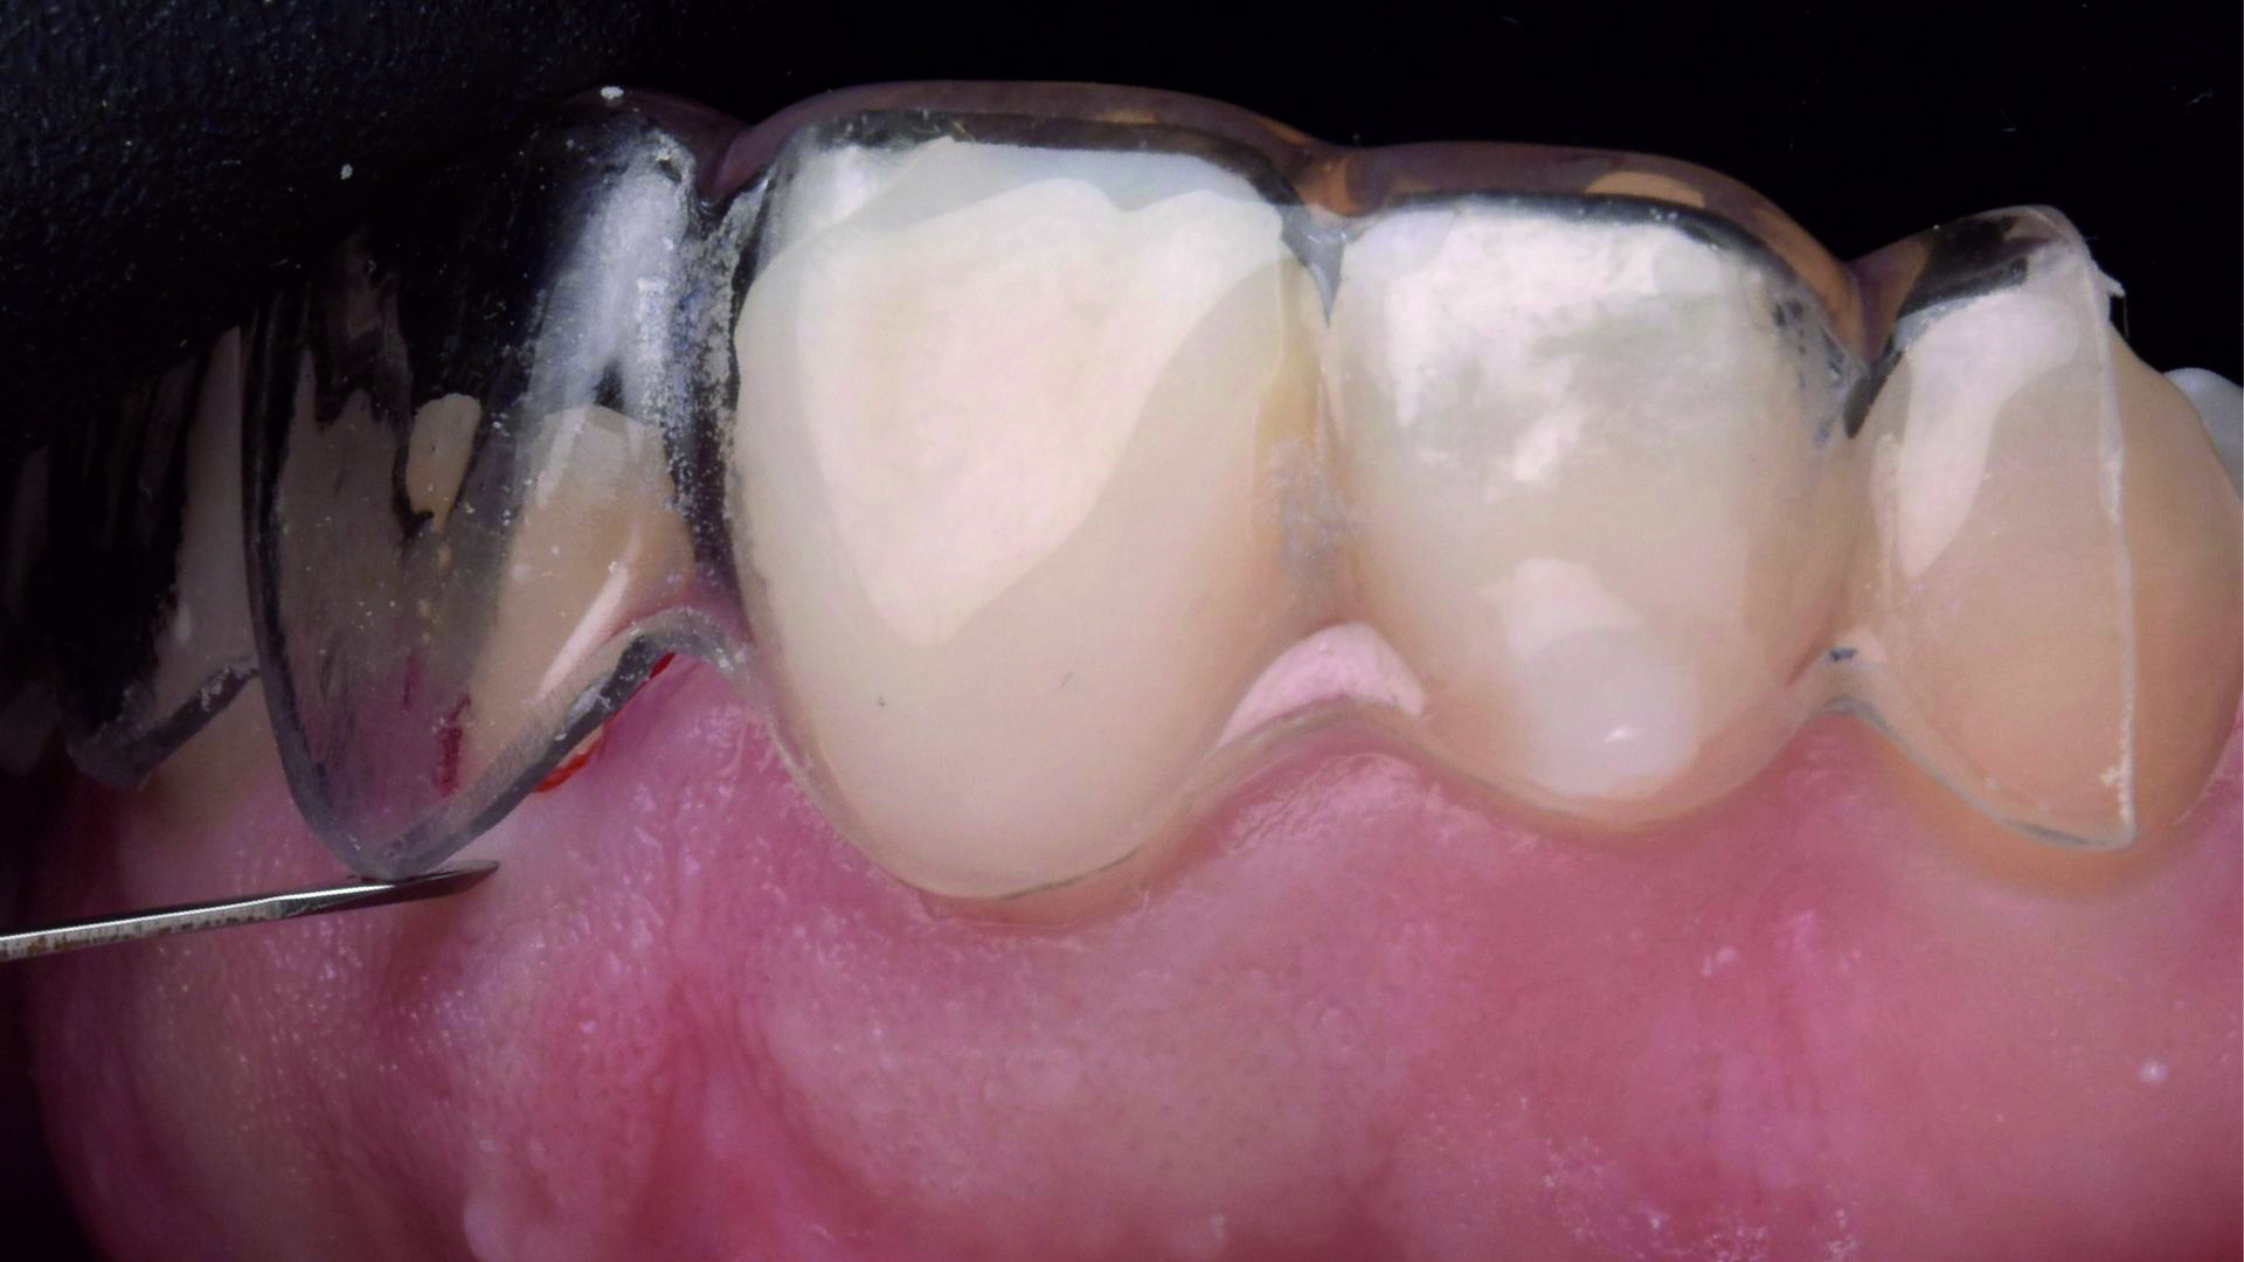

Фото 18. Після установки першої ретракційної нитки, просоченої хлоридом алюмінію, ми також виконали електрохірургічну підготовку і нанесли ретракційну пасту, сподіваючись отримати чіткі кордони препарування та добрий контроль виділення рідини.

Фото 22. Щоб краще відкрити глибокі краї була використана техніка подвійної нитки. Це означає, що першу ретракційну нитку слід помістити в ясенну борозенку для вертикальної ретракції ясен і залишити там, а другу – частково занурити у борозенку для горизонтальної ретракції та видалити безпосередньо перед зняттям відбитка.